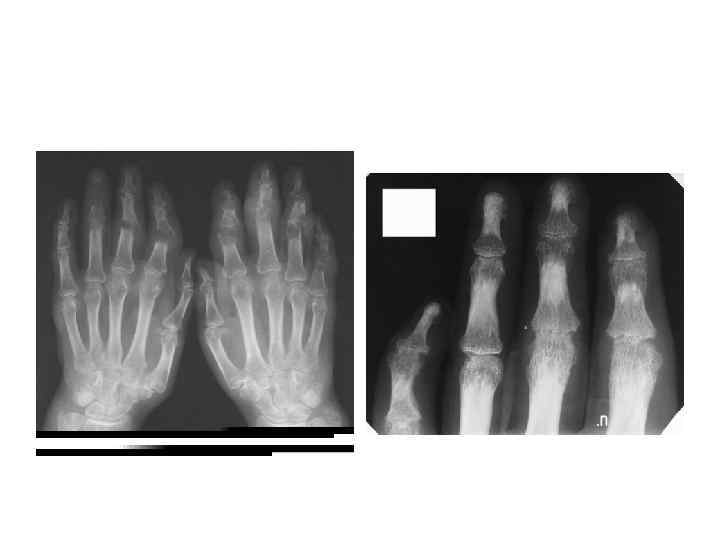

КЛАССИФИКАЦИЯ РА (3) Рентгенологическая стадия (по Штейнброкеру) • I – околосуставной остеопороз • II- остеопороз + сужение суставной щели (могут быть единичные узуры) • III – то же + множественные узуры • IV – то же + костные анкилозы

Общая рентгенологическая картина • Повреждение хряща (сужение суставной щели) • Костная эрозия

Классификационные критерии подагрического артрита (Wallace с соавт. , 1977 г, рекомендованы ВОЗ в 2000 г) А. Наличие характерных кристаллов моноурата натрия в суставной жидкости (абсолютный критерий) Б. Наличие тофусов, содержание кристаллов моноурата натрия в которых подтверждено химически или поляризационной микроскопией (абсолютный критерий) В. Наличие 6 из 12 ниже перечисленных признаков: 1. Более одной атаки острого артрита в анамнезе 2. Воспаление сустава достигает максимума в 1 -й день болезни 3. Моноартрит 4. Гиперемия кожи над пораженным суставом 5. Припухание и боль в первом плюснефаланговом суставе 6. Одностороннее поражение первого плюснефалангового сустава 7. Одностороннее поражение суставов стопы 8. Подозрение на тофусы 9. Гиперурикемия 10. Асимметричный отек суставов 11. Субкортикальные кисты без эрозий (рентгенография) 12. Отрицательные результаты при посеве синовиальной жидкости Wallace SL, Robinson H, Masi AT, Decker JL, Mc. Carty DJ, Yu T-F. Preliminary criteria for the classification of the acute arthritis of primary gout. Arthritis Rheum 1977, 20, 895 -900

Дополнительные методы обследования • Рентгенография 1 плюснефалангового сустава и кистей • Содержание мочевой кислоты (0, 36 - 0, 42 ммоль/л) • Поляризационная микроскопия